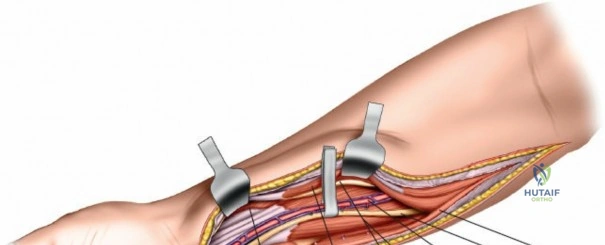

Exposure and Release of Deep Volar Compartment: This is the most critical and potentially challenging step. The median nerve and ulnar artery lie deep to the superficial flexor muscles.

- Median Nerve Protection: Retract the FDS radially. The median nerve typically lies beneath the FDS. It must be carefully identified and protected.

- Ulnar Nerve and Artery Protection: The ulnar nerve and artery run along the ulnar border, deep to the FCU. They are usually not directly in the field of the primary fasciotomy, but their fascial envelopes should also be released.

- Accessing the Deep Compartment: Separate the FDS radially from the FCU. Retract the FDS radially and the FCU ulnarly. The deep volar compartment, containing FDP, FPL, and PQ, is now accessible. The fascia overlying the FDP and FPL must be meticulously incised longitudinally. This deep release is crucial for adequate decompression.

This image illustrates the deeper dissection. The superficial flexor muscles (FDS) are retracted, exposing the median nerve and the underlying deep volar compartment. Note the care taken to protect the median nerve.

The median nerve and ulnar artery/nerve must be completely unroofed to ensure adequate decompression. This often requires releasing the entire carpal tunnel proximally to ensure distal decompression of the median nerve.

This detailed view highlights the median nerve (retracted by the yellow vessel loop) and the extensive release required, extending distally to encompass the carpal tunnel, ensuring complete decompression.Ensure that the deep fascia separating the FDS from the FDP and FPL is completely released. The anterior interosseous nerve and artery lie on the interosseous membrane and should also be decompressed by releasing the fascia overlying the deep flexors.

Further meticulous dissection showing the complete release of the deep volar compartment, with all muscle bellies visibly decompressing. Neurovascular structures are clearly identified and protected.